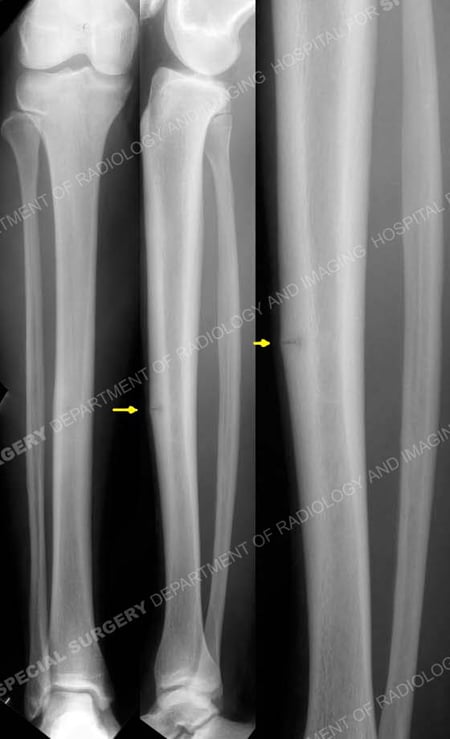

Anteroposterior and lateral radiographs reveal a stress fracture of the anterior tibial cortex (arrows).